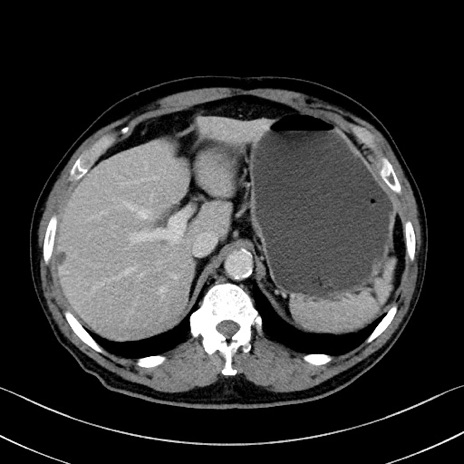

症例35(横断像)

【症例】70歳代 男性

【主訴】腹部膨満、嘔吐

【現病歴】昨日より腹部膨満感出現。本日増悪し、仙痛出現。嘔吐あり、受診。

【既往歴】糖尿病、胆摘後

【身体所見】BP 149/80mmHg、HR 74/min、BT 35.9℃、腹部:膨満、軟、圧痛なし。腸雑音減弱あり。上腹部正中切開瘢痕あり。

【データ】WBC 13500、CRP 1.72